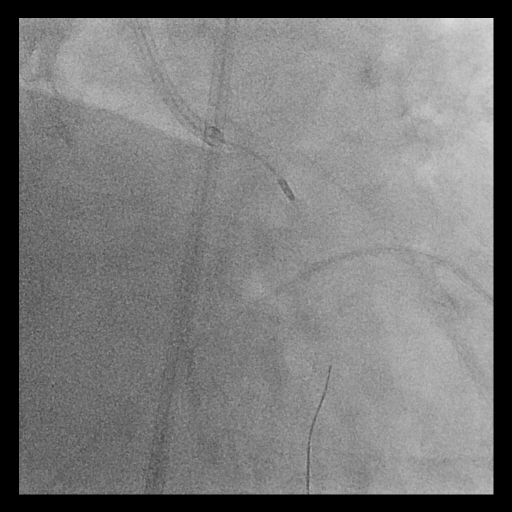

Procedural Step

Given the extensive and concentric calcium across the LM bifurcation, an upfront ¡°Rotatripsy¡± strategy (rotational atherectomy followed by intravascular lithotripsy) was selected. A 1.25 mm burr was used for initial channel creation in the LCx and LM-LAD, with transient bradycardia requiring temporary pacing. Post-rotablation IVUS revealed residual deep calcium. Subsequently, intravascular lithotripsy (IVL) using a 3.5–4.0 mm balloon (1:1 sizing to proximal LCx and LM) was applied with 8 cycles, achieving clear calcium fracture on IVUS. Two DES were implanted sequentially (LCx: 3.5¡¿28 mm; LM–LAD: 4.0¡¿38 mm), followed by high-pressure post-dilation and final kissing balloon inflation. Final IVUS confirmed optimal stent expansion (MSA: LCx 7.7 mm©÷, LAD 12.1 mm©÷, LM 13.2 mm©÷) and well-apposed stents throughout the bifurcation.